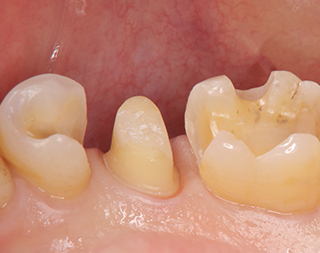

クラウン(かぶせ)、インレー(詰め物)など、耐久性、審美性、機能性の高い歯科素材を使用し、

形と色を揃え、天然歯と同じような見栄えを実現します。

大幅に削り取った歯でもコアという土台を創り、審美ほてつで形成して見栄えをよみがえらせることも可能です。